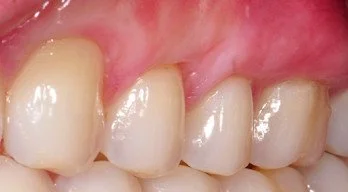

Close-up of upper front teeth with gingival recession on teeth #11-14.

Before

Close-up of a set of upper teeth showing gingival recession defects on teeth #11-14 successfully covered with gum grafts.

After